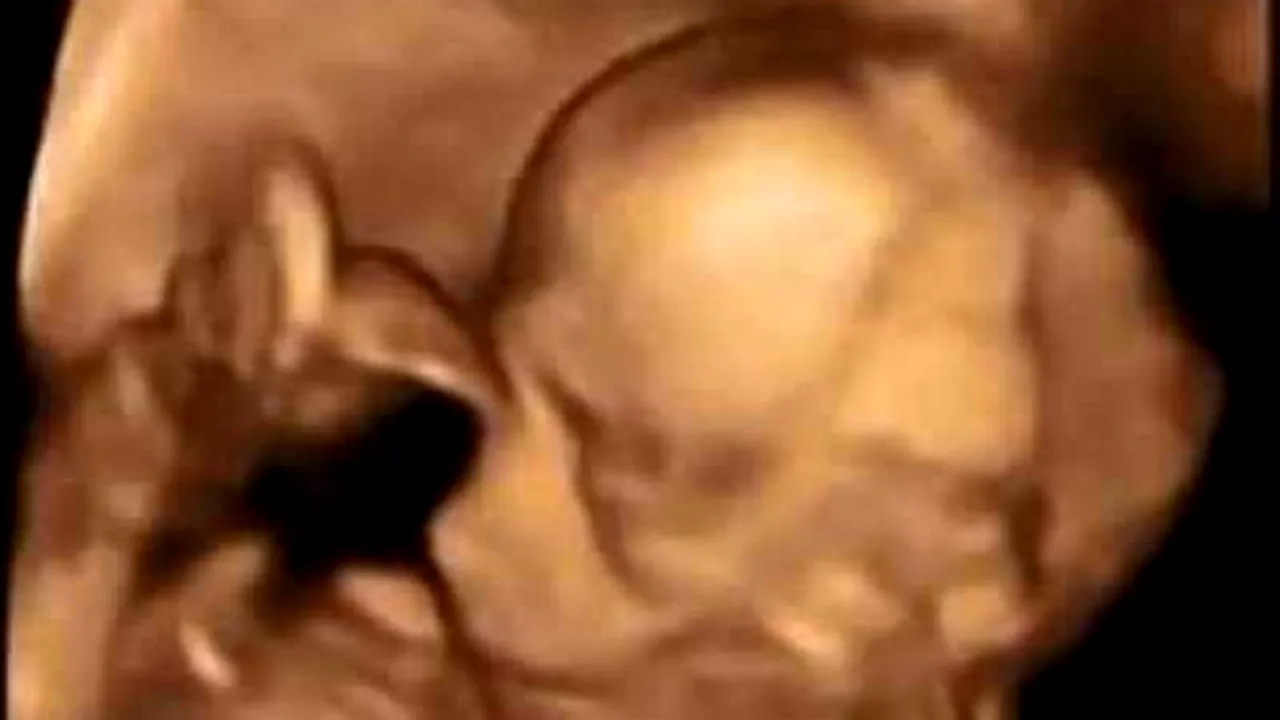

Sarah și Bill Imbierowicz, doi părinți din statul american Indiana, sunt în stare de șoc, după ce au aflat că vor avea tripleți, la doar 15 luni după ce primii tripleți au apărut în familia lor. Cuplul mai are patru băieți, dar de data asta cei doi își doreau o fetiță, motiv pentru care au apelat la fertilizare în vitro. La ecografie însă au aflat vestea care i-a uimit pur și simplu: vor avea trei fete.

Ceva mai târziu, cei doi au reluat procedura, crezând că se va întâmpla același lucru, dar s-au născut trei băieți. Ultima oară au fost implantați doi embrioni și au rezultat trei fetuși, așa încât trei fetițe vor veni pe lume prin cezariană la începutul anului viitor.